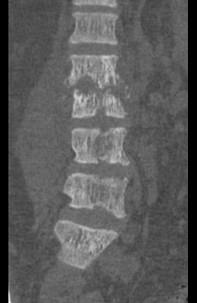

问题 男,67岁,背痛,发热,寒战半月余,有镰状细胞贫血病,请结合影像学检查,选择最可能的诊断 ( )

选项 A、脊髓空洞症 B、脊柱骨髓炎 C、椎体压缩骨折 D、脊柱转移瘤 E、脊柱结核

答案 B